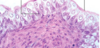

This type of epithelial cell is actually attached to the basement membrane even though it sometimes doesn’t appear to be that way Where two places are they commonly found?

Simple Pseudostratified Upper Respiratory Tract and trachea

Look at diagram for pseudostratified epithelium and know goblet cells, basal cells, epithelial cells, basement membrane, lamina propria, terminal bars, mucua, cilia, etc